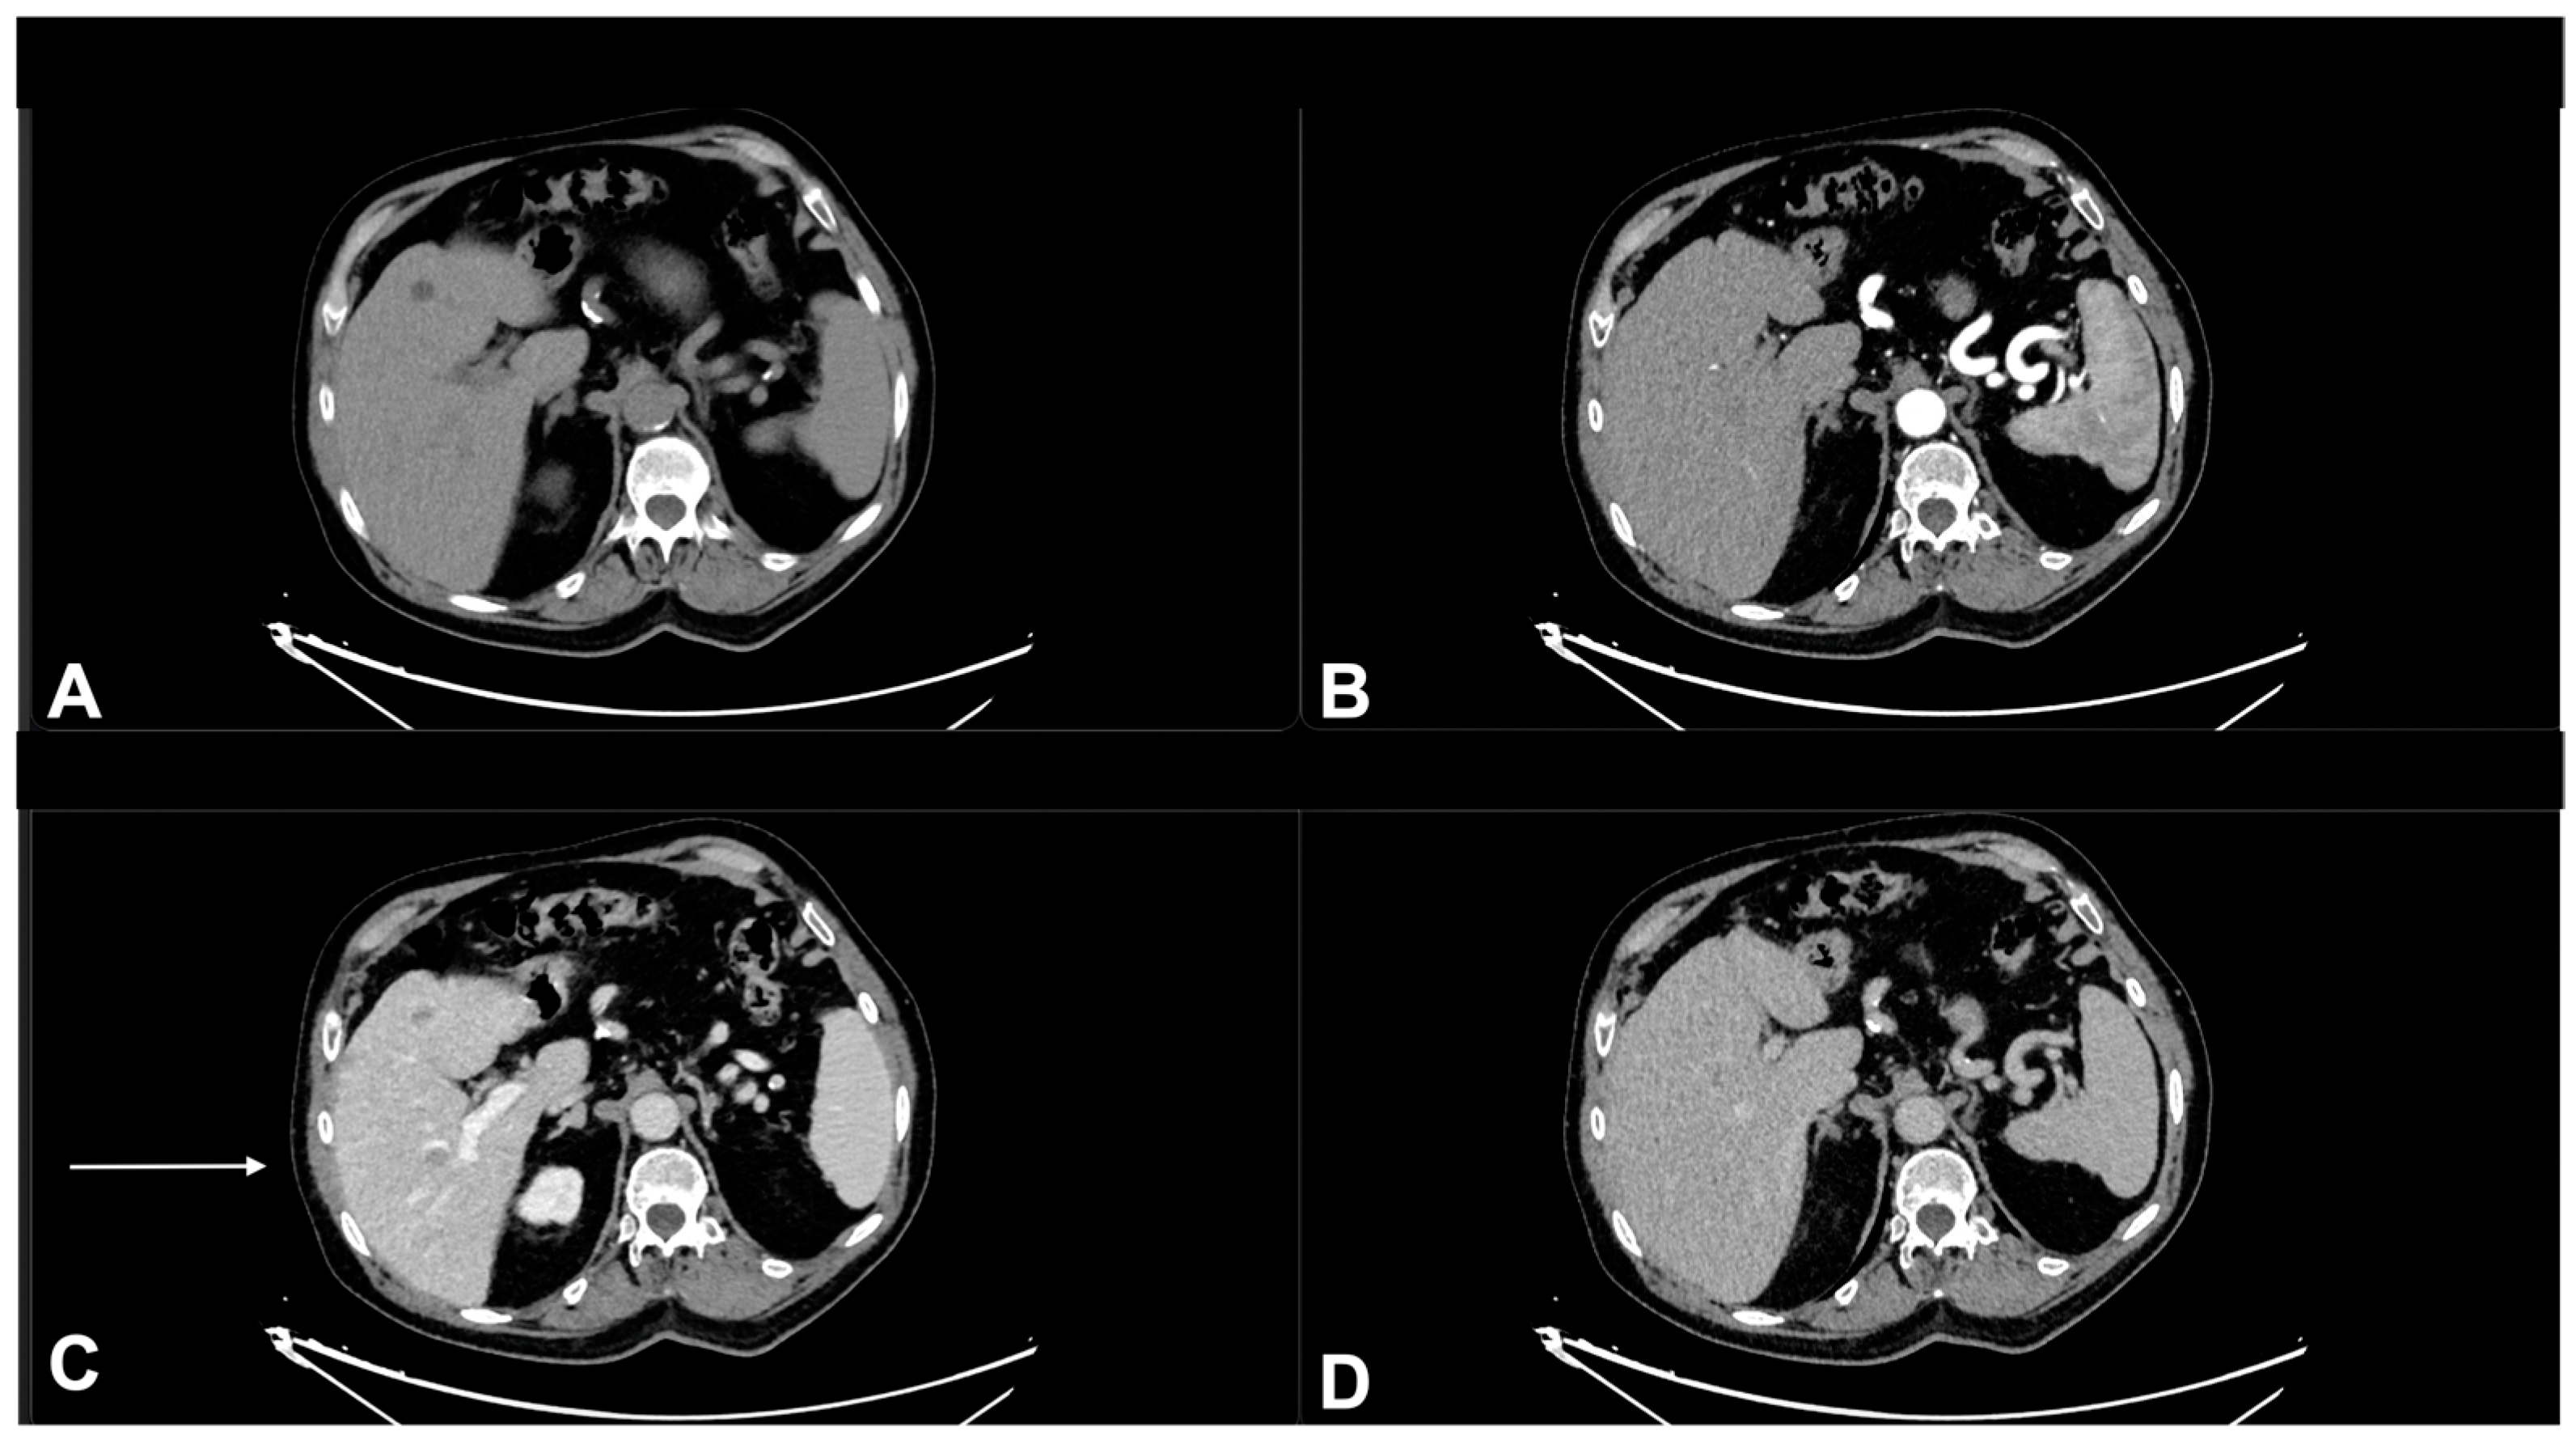

- Granata, V.; Fusco, R.; Piccirillo, M.; Palaia, R.; Petrillo, A.; Lastoria, S.; Izzo, F. Electrochemotherapy in locally advanced pancreatic cancer: Preliminary results. Int. J. Surg. 2015, 18, 230–236. [Google Scholar] [CrossRef] [PubMed]

- Granata, V.; Fusco, R.; Setola, S.V.; Piccirillo, M.; Leongito, M.; Palaia, R.; Granata, F.; Lastoria, S.; Izzo, F.; Petrillo, A. Early radiological assessment of locally advanced pancreatic cancer treated with electrochemotherapy. World J. Gastroenterol. 2017, 23, 4767–4778. [Google Scholar] [CrossRef] [PubMed]

- Tirkes, T.; Hollar, M.A.; Tann, M.; Kohli, M.D.; Akisik, F.; Sandrasegaran, K. Response Criteria in Oncologic Imaging: Review of Traditional and New Criteria. Radiographics 2013, 33, 1323–1341. [Google Scholar] [CrossRef] [PubMed]